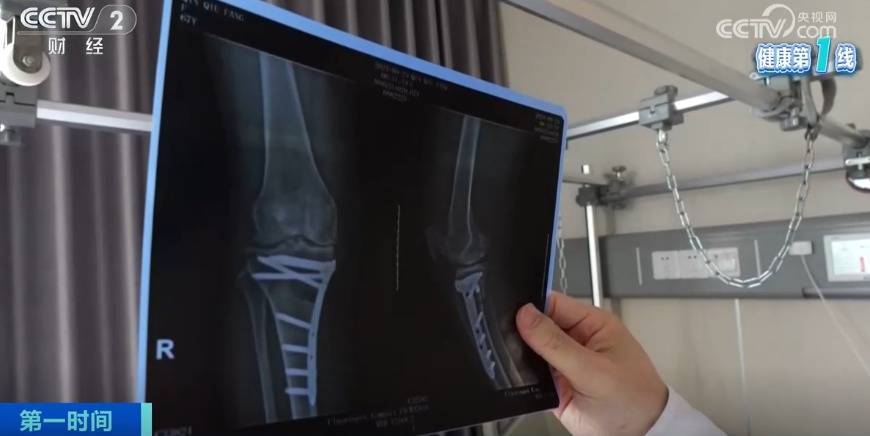

r北京大学人民医院骨关节科副主任医师 王锴:关节置换最成熟的就是下肢的负重关节,包括膝关节和髋关节,之前做一个进口关节(置换手术)自费是五六万元,目前一个患者的自费花费可能比原来的一半还要低。